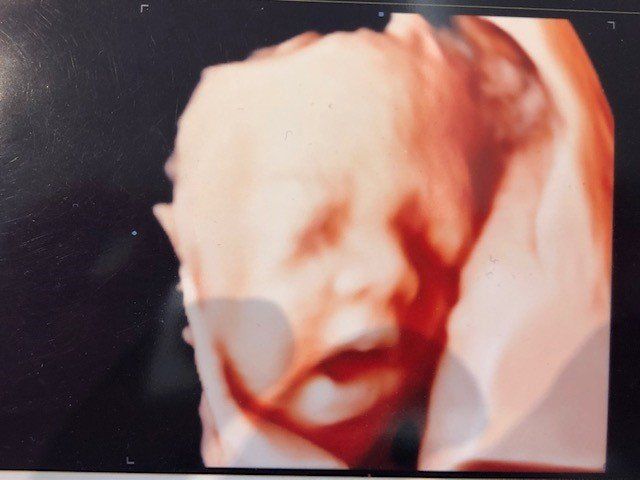

e’ specializzato in Ostetricia e Ginecologia. In campo Osterico esegue Ecografie del Primo trimestre, screening, esame premorfologico della gravidanza a rischio, ecografia morfologica di primo e secondo livello con studio cardiaco fetale, ecoflussimetria, valutazione ecografica in 3d e 4d con registrazione su supporto digitale DVD o Pen Drive per le pazienti. In campo ginecologico ecografia di primo, secondo livello e studio delle Masse Ovariche secondo le linee guida internazionali IOTA.

Lo specialista in Ostetricia per le pazienti in dolce attesa propone un piano di controllo estremamente dettagliato, ad esempio oltre alla classica ecografia che solitamente viene eseguita nei primi mesi della gravidanza, si esegue anche l'esame premorfologico per le gravidanze a rischio, in modo da valutare fin dai primi mesi la probabilità di malformazioni ed ecografia 3d e 4D con registrazione su supporto digitale delle immagini e del suono del battito cardiaco. Si effettua lo studio cardiaco fetale, tutto ciò consente di monitorare e tutelare la salute della madre e del bimbo.